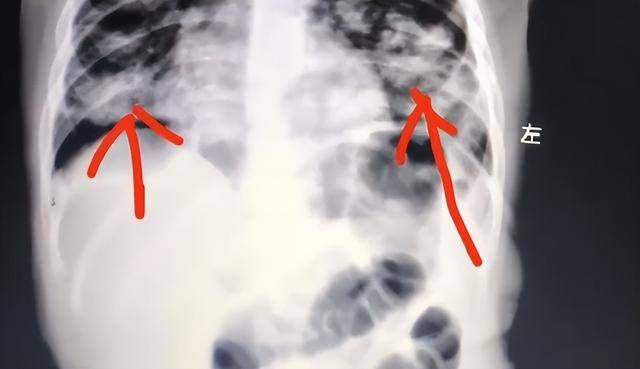

家长发现后,第一反应是立即用手抠孩子喉咙催吐,不料这一做法反而导致油脂被吸入肺部,引发严重吸入性肺炎世界杯皇冠信用平台。目前,孩子肺部已出现大面积感染变白。

油脂类物质一旦进入肺部,难以自行排出,会迅速引发炎症和感染,情况十分危险世界杯皇冠信用平台。